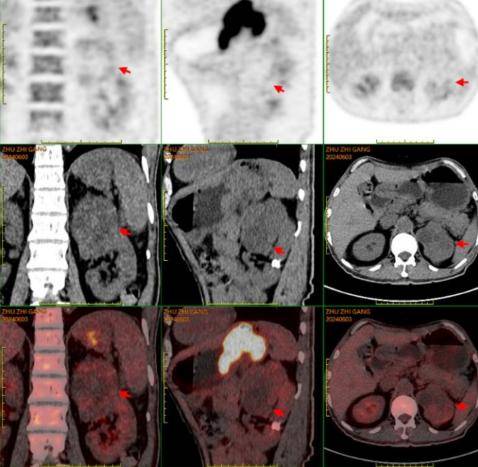

PET/CT:贲门部、胃底部及胃体部胃壁增厚、局部软组织密度肿物形成,葡萄糖代谢增高,考虑恶性可能性大(胃癌?)。肝胃之间多发葡萄糖代谢增高淋巴结,考虑转移可能大。左肾上极混杂密度肿物,内伴钙化及坏死,葡萄糖代谢增高,考虑恶性可能性大(肾癌?)。

疗效评估:复查影像学显示贲门胃小弯侧肿瘤、肝胃间隙转移淋巴结及左肾占位均较前缩小。

术后病理:①近端胃标本提示肿瘤达到pCR,肿瘤退缩分级(TRG)为0级(完全退缩)。②左肾及肾上腺:透明细胞性癌,WHO/ISUP核分级II-III级,脉管内癌栓、神经侵犯(-),肿瘤大小约5.5*5*3.5cm,肾盂肾窦、肾周脂肪及肾上腺未见癌侵及标本病理为透明细胞性肾细胞癌,WHO/ISUP核分级II-III级,分期pT1bN0Mx。